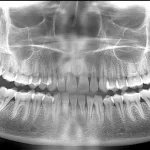

The Eight Most Common Reasons that Your Dental Panoramic X-Ray Image Does Not Look Good (and How To Avoid Them)